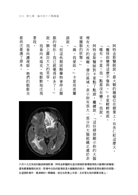

她腦中18顆致命的轉移型黑色素瘤,徹底地讓她的日常消失殆盡。

二○一五年六月,我的心智在毫無預警的情況下,突然出現了奇怪又可怕的轉變。這一切都起因於在我大腦裡作祟的轉移型黑色素瘤,所以我大概有兩個月的時間,都因它呈現一種精神錯亂的狀態。當然,我當下並無自覺。後來之所以能夠突破黑色素瘤覆在我心智上的黑幕,都是多虧老天眷顧、現代醫學的進步,還有家人的警覺和支持。

當一個人的行為舉止因為腦瘤出現轉變時(跟我一樣),似乎比較容易從神經學和行為學的角度建立其病況的因果關係。理論上,神經科醫師都希望每一項精神疾病症狀,可以直接反映大腦某一特定腦區的異常。而在原發性腦瘤的情況下,神經科醫師的這類願望大多可以如願以償。只不過,假如是轉移性腦瘤,那就是另一種景況了;因為不論這些轉移性腦瘤是因黑色素瘤、乳癌或肺癌而生,它們通常都會同時影響腦部的多個區塊,讓神經科醫師難以判斷患者的行為異常,到底是由哪一個受影響的腦區所致。又或者,萬一你跟我一樣,腦袋裡同時長了兩顆以上的腫瘤,在這種情況下,也很難判定其行為轉變是因大腦何處異常所致。再者,腫瘤本身和治療的過程,也會造成腦組織腫脹,對大腦形成壓迫,這些在在都會致使患者的行為出現不同以往的變化。

等我的心智終於突破那片黑幕,重拾清醒的思路後,身為一名神經科學家,我當然想搞清楚自己的大腦在那段時間裡出了什麼問題。而當我知道主要是額葉(編注:主要掌管語言形成、表達、自主意識等)和頂葉(編注:主要掌管各類感覺訊息,同時也和語言、記憶等功能有關)出了狀況時,很快就明白那時候我為什麼會出現如此多與精神疾病患者相似的行為舉止,因為這兩個腦區掌管了許多最人性化的行為。比方說,那段期間我曾在熟悉的地方迷失了方向,忘記剛剛才發生在自己身上的事,對家人的態度變得既暴躁、刻薄又冷漠;老是斤斤計較早餐吃什麼這類枝微末節的奇怪小事,卻無視自己即將死亡的事實。我甚至完全沒注意到自己在不知不覺間產生了這些轉變。換句話說,即便那時候我的心智逐漸退化,但從頭到尾我都渾然未覺自己正陷入精神疾病的窘境。